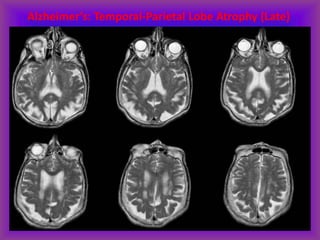

Irreversible dementias (imaging non-

specific):

• Alzheimer’s disease

• Multi-infarct dementia

• Dementias associated with

Parkinson’s disease and similar

disorders

• AIDS dementia complex

Alzheimer’s: Temporal-Parietal Lobe Atrophy (Late)